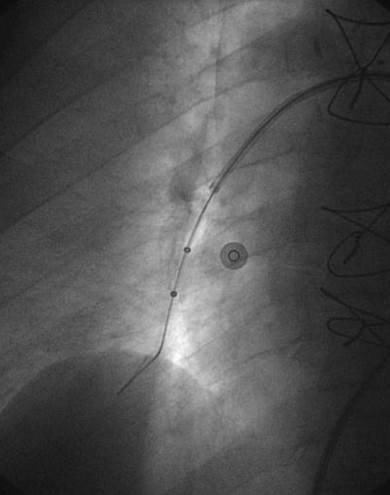

Angiografía de la arteria pulmonar derecha realizada con un catéter en espiral de 6 F en ángulo, que demuestra la presencia de un trombo de gran tamaño dentro de la arteria pulmonar derecha y en las bifurcaciones lobulares intermedia, inferior y superior.

Se efectuó una trombectomía reolítica con el catéter PE de AngioJet® mediante un catéter guía multifunción de 8 F y una guía de angioplastia hidrófila de 0,035’’, en las bifurcaciones lobulares intermedia e inferior.

Angiografía pulmonar derecha realizada tras una trombectomía reolítica en la que se muestra la mejora de los índices de perfusión y obstrucción.